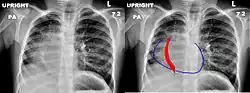

Le nom de ce syndrome vient de l'aspect angiographique du vaisseau anormal dont la forme, oblique en bas et en dedans, s'élargissant de haut en bas, évoque celle d'un cimeterre[3].